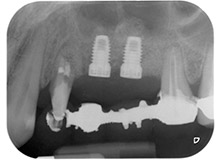

The implants (Restore, Keystone Dental, diameter 3,75 mm, length 8.0 mm) were placed with the implant motor (Figs. 11 and 12).

Fig. 12: Both implants in place and ready for the cover screws.

Finally, after periosteal incision, the site was passively sutured with a coronally advanced flap, using 5-0 absorbable suture material (Fig. 15). The postoperative radiograph showed both implants in their correct vertical position (Fig. 16).

Fig. 16: Postoperative radiograph showing the implants in place, with bone substitute material from the internal sinus lift around the apices. There is some material from the GTR procedure visible around the roots of tooth 24.